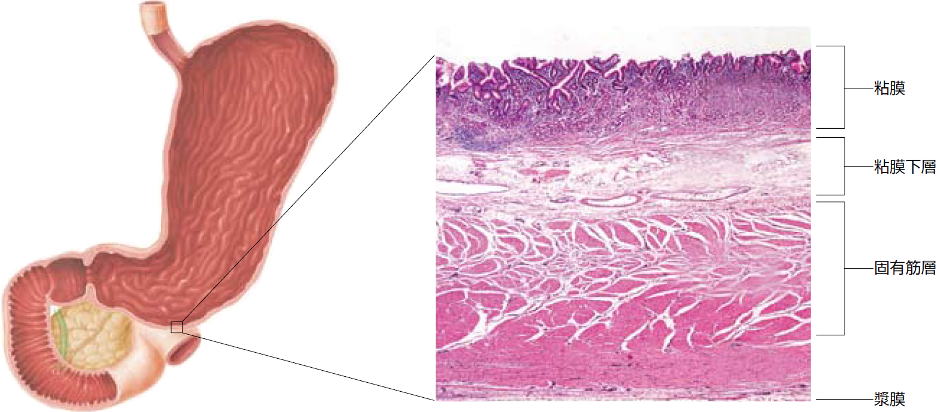

| ژه‚بˆفپEڈ\“ٌژw’°ژ¾ٹ³ | |

| ڈ\“ٌژw’°’×ل‡ | ڈ\“ٌژw’°SMT |

| ڈ\“ٌژw’°ٹàپi‚ك‚¸‚炵‚¢ڈا—ل‚إ‚·پj | “¯ڈا—ل‚جNBI‰و‘œپiژîل‡ŒŒٹا‹’²ژB‰eپj |